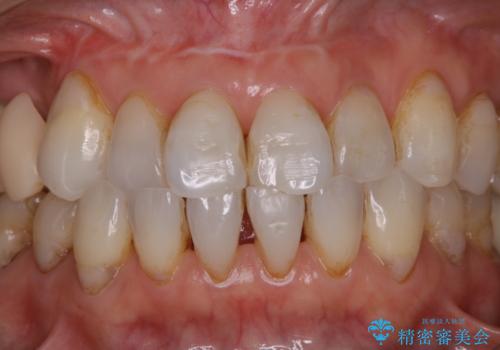

歯のクリーニングPMTC60分コース

- 色が気になるため、全体的にお口のお掃除を希望とのことで来院されました。PMTC60分コースを行いました。

毎日丁寧に歯磨きをしていても、日常生活での飲食物などにより着色してしまうことはあります。PMTCでは、歯の表面の凸凹にミネラルを補給して、ツルツルの表面に仕上げます。定期的にPMTCを行うことにより、歯質の強化になり着色がつきにくい状態になります。